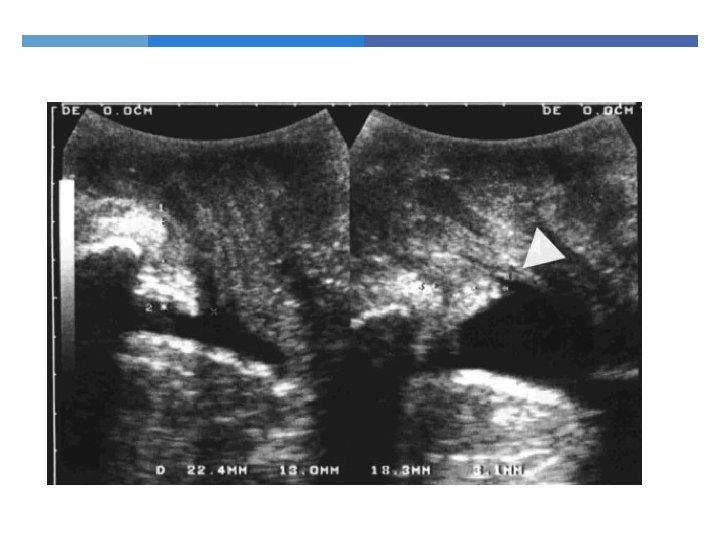

Endoanal Ultrasonography 360 degree rotating probe Simple and relatively painless Excellent visualization of the 5 layers of the anal canal

Endoanal Ultrasonography Muscle thickness Scarring Loss of muscle tissue

Endoanal Ultrasonography